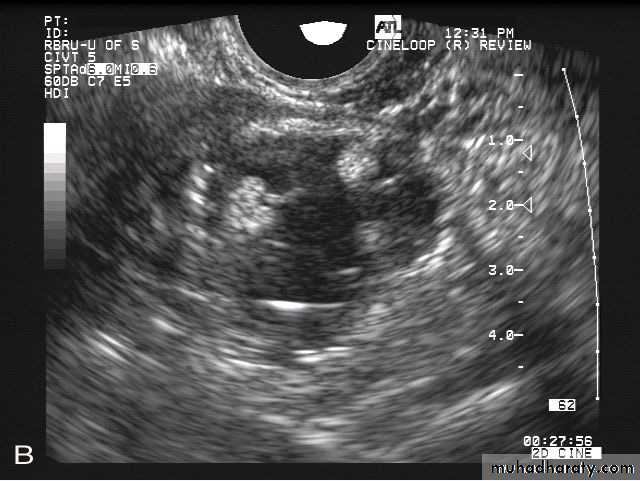

Transvaginal ultrasound images of ovarian hyperstimulation syndrome:This young adult female patient showed multiple large theca lutein cysts of both ovaries, arranged in spoke-wheel pattern (ultrasound images above) which were the result of use of gonadotropins in the management of infertility. The cysts vary in size from 2 to 4 cms. with the ovaries massively enlarged (each ovary measures up to 7 cms. in size). This can be classified as grade-2 hyperstimulation of the ovaries (ovarian diameter from 5 to 10 cms.). There is not evidence of ascites. The color Doppler image of the ovaries shows vessels passing along the margins of the cysts. One of the complications of such enlarged ovaries in OHSS is torsion and in certain cases rupture of the ovaries, both of which are medical emergencies. Ovarian hyperstimulation syndrome is known to occur more frequently in patients of pre-existing Polycystic ovaries (PCO).